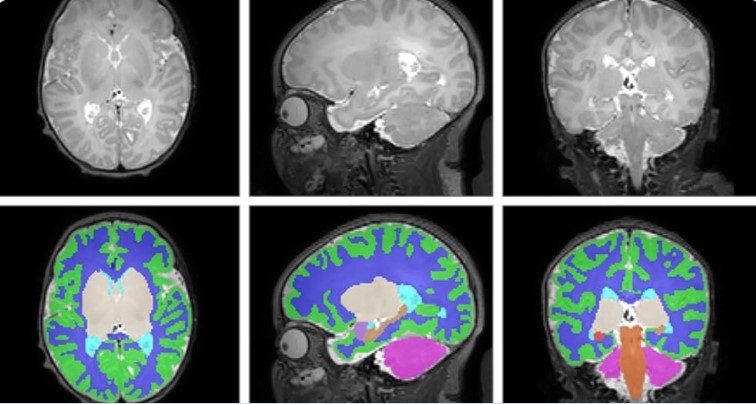

Total brain volume was nearly 5% smaller among 173 newborns with antenatal opioid exposure compared to 96 unexposed newborns, based on magnetic resonance imaging (MRI) scans. More specifically, reduced volumes among opioid-exposed newborns occurred in cortical gray matter, deep gray matter, white matter, cerebellum, brainstem, and the right and left amygdala. There were notable differences in the location and scale of the effects, which varied depending on the type of opioid involved, and whether other drugs were also taken during pregnancy.

“We have known for a while that children exposed to opioids during pregnancy are at risk of later developmental and behavioral problems, but it was hard to know whether that was due to the opioids themselves or other factors such as other exposures or lower birth weight,” says co-first author Stephanie Merhar, MD, MS, a neonatologist at Cincinnati Children’s. “This study was launched because we needed a large study where we were able to control for things like nicotine exposure and birth weight. Our next step is to follow the children in the study to see whether having smaller brain volumes in the newborn period affects later development and behavior.”

Other small studies have shown fetal brain changes caused by opioids. But this multi-center study is the first to be large enough to convincingly distinguish effects linked to opioids versus confounding factors such as maternal smoking, birth weight, education levels.

The study authors “present compelling evidence of the direct effects of opioids on the developing brain,” the editorial states. “Given the prospective design of the trial, they account for other postnatal factors…allowing us to dispel previous uncertainty surrounding the direct impacts of opioids on the brain vs the confounding effects of other environmental factors.”

Having more precise information about the affected parts of the brain could allow scientists to focus on interventions to support healthy brain development for children born after opioid exposure.